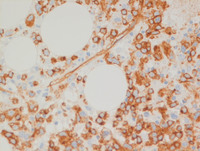

Figure 6: Bone marrow biopsy-CD34

Blasts expressing CD34 (small CD34+ cells-Left image) are seen admixed with dysplastic megakaryocytes staining with CD34 (white arrow-Right image). Such aberrant staining by dysplastic megakaryocytes is non-specific and is frequently seen in malignant myeloid processes.